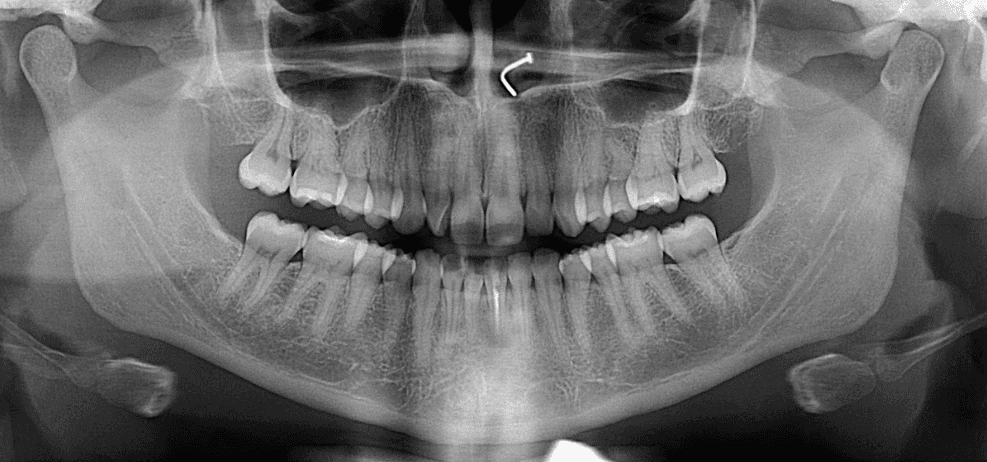

Initial treatment

X-RAYS